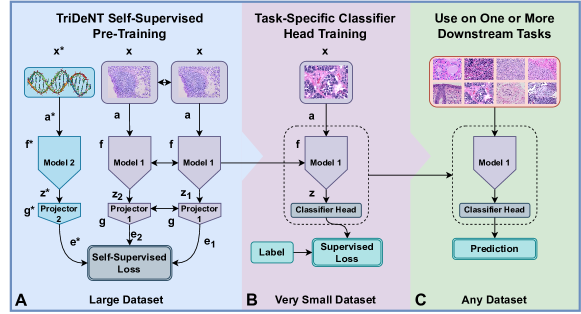

Self-supervised LUPI training has been shown to be a highly effective method of improving the performance of models whose privileged data contains more task-relevant information than the primary data [19, 20]. These methods are designed to minimise the difference between the representations of each input by mapping all embeddings into a shared latent space (joint embedding) [21]. However, in the case where we are only interested in the output of one branch, this can be restrictive. For example, if a feature is not shared between both inputs, these methods will neglect it, leading to worse performance [19] (Figure 1(a), see Sections 4.3 and 4). This was apparent in [20], where, despite impressive retrieval performance, the proposed joint embedding model significantly underperformed supervised models on classification tasks, implying that important features were neglected in the primary domain. In this work we present TriDeNT ♆ (Figure 1(b), Section 4.4), a new method designed to enable features which are only present in the primary data to be learned in addition to those shared between inputs. The main contributions of this work are:

4.4 TriDeNT ♆

The goal of TriDeNT ♆ method is to combine the benefits of both LUPI and non-LUPI methods in such a way that the primary encoder can make best use of signals from all inputs. We use a three-pronged approach, with two branches acting on the primary input and a third acting on the privileged input. Our method can be considered a generalisation of the standard Siamese self-supervised architecture. We take inputs , where we assume each input contains some information about their shared source. The inputs could represent any type of input array, such as images, -omics data, or patient information. We assume contains some mutual information with . We aim to obtain representations , such that the is a sufficient representation of for some task , that is to say we have mutual information . Note that, in contrast to comparable approaches, we are only interested in optimising insofar as this benefits , as only is to be used for inference.

Inputs are augmented by stochastic operators

| (1) |

respectively, and mapped to representations by encoders according to the rule

| (2) |

We have defined to be if its input is and if its input is , as in general there is no reason for augmentations to be the same for primary and privileged data. This yields three representations, , and , where and are representations of each augmentation of the primary data, and is the representation of the privileged data. Representations are then mapped to embeddings by a projector with the rule . In general we will have primary encoder and projector .

Note that the spaces and are not dependent on , as these are shared latent spaces. Projections into an embedding space are used in keeping with existing approaches [13, 14, 12], as this has been shown to improve generalisation and feature learning. For inference, augmentations are not applied, so is set to . In general, we use the same encoder for both branches taking as input, as sharing weights has been shown to improve performance on unprivileged tasks [19]. Typically, we will have where is the batch size and is the dimension of the representation. For pseudocode, see Algorithm S1.

4.6 Primary and Privileged Features

For an intuitive understanding of the method, it is helpful to consider the representation of each branch as a supervisory signal for the others. Our model can therefore be considered a multi-objective setting, where the primary encoder aims to balance the information extracted from each augmentation of which is shared with , and that which is shared with the other augmentation of . In turn, the supervisory signals for are and , and consequently they will only extract features which can also be found in . In our typical setting, this corresponds to balancing information which is only weakly present in the primary input , but strongly present in the privileged input , with information which is strongly present in primary input . The result of this trade-off is that privileged features with a strong supervisory signal from and are learned, but primary features with a strong supervisory signal from from are also learned. This is in contrast to the dichotomy between only learning strong features or only learning shared features presented by the standard 2-branch approaches.